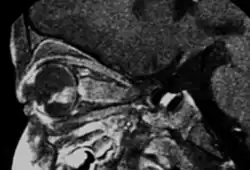

- MRI: assessment of local extension to optic nerve, anterior chamber, and orbital fat. Slightly hyperintense on T1, hypointense on T2. Also to rule out trilateral retinoblastoma

- CT: intraocular mass with a higher density than the vitreous body, calcified in 90% of cases and moderately enhanced after iodine contrast agent injection. However, should be minimized due to ionizing exposure, particularly in heritable cases